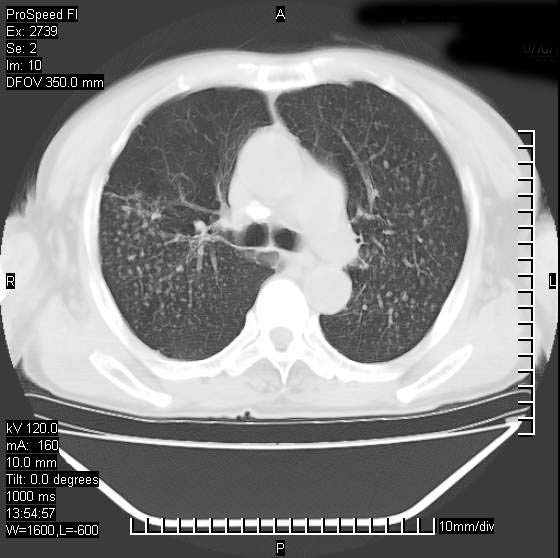

以下是引用andymaomao在2007-12-7 15:54:00的发言:[br]1.双上肺陈旧肺tb灶;[br]2.双中上肺矽肺;[br]3.双肺气肿;[br]4.图中箭头所指乃下腔静脉。

以下是引用山之魂海之韵在2007-12-7 18:59:00的发言:[br]支持矽肺,左肺上叶陈旧性结核,肺气肿。箭头所指乃下腔静脉。下腔静脉显影比主动脉显影迟,增强动脉后迟可以是不均匀的。

以下是引用chengjiaqiu1在2007-12-7 17:49:00的发言:[br]矽肺,左肺上叶陈旧性结核,肺气肿。中箭头所指乃下腔静脉。